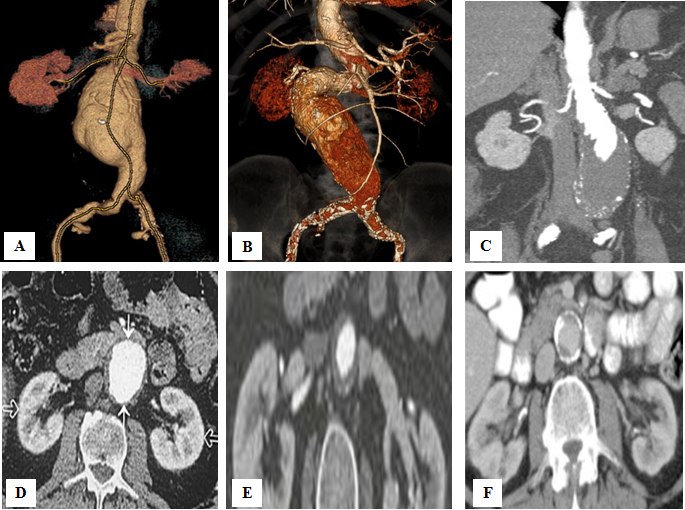

The aneurysmal anatomy is the first factor that can make standard EVAR more difficult or even impossible. According to an FDA study that examined the eligibility of infrarenal AAA for on-label EVAR, 35% of male and up to 60% of female patients were unsuitable for standard EVAR because of problems with aneurysmal neck or iliac access [7]. Severe tortuosity and small diameter of iliac arteries (<6 mm) are the first anatomic limitations for EVAR. However, the characteristics of the aneurysmal neck play a much more important role. A Delphi Consensus document that defines five aneurysm neck hostility criteria (aortic neck diameter, aortic neck angulation, conical neck, aortic neck length, circumferential calcification) was created by nine Italian vascular surgeons from high-volume centres (>50 EVAR procedures/year) in 2019 [8]. This document identified the following categories of patients: those in whom standard EVAR is feasible; those in whom standard EVAR is not the first choice due to anatomic conditions; those in whom standard EVAR is not advised due to moderate risk of failure; those in whom standard EVAR is not advised due to high risk of failure; finally, those in whom standard EVAR is not applicable. According to these criteria, a standard EVAR is not applicable when aneurysmal neck has the following characteristics: length <10 mm, width >32 mm, angulation >750, circumferential calcification of at least 50%, as well as conical shape [8] (Figure 1).

222_Davidovic_FIgure 1 - Is there a role for open repair of abdominal aortic aneurysms in the endovascular era.jpg